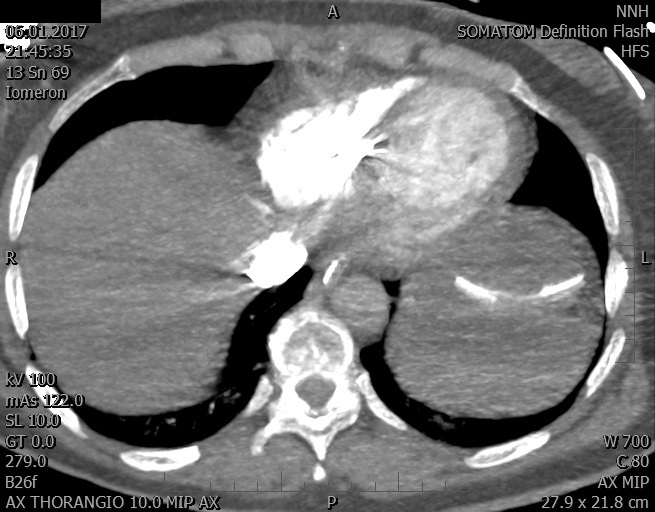

Video 1 - Akutní koronarografie prokázala normální nález na věnčitých tepnách s výjimkou suspekce na lehký spasmus na pravé koronární tepně.Echokardiograficky byla zjištěna těžká dysfunkce dilatované levé komory s nezvětšenou pravou komorou (video 2).

Video 2 - Echokardiograficky byla zjištěna těžká dysfunkce dilatační levé komory s nezvětšenou pravou komorou.Pro nejasnou příčinu zástavy jsme provedli i vyšetření výpočetní tomografií (CT), které vyloučilo plicní embolizaci (série 1 - soubory na konci článku). V den přijetí při přetrvávající oběhové nestabilitě byla nemocná opakovaně defibrilována pro fibrilaci komor se stabilizací rytmu po podání amiodaronu a mesocainu. Dle hemodynamických měření se jednalo o těžký kombinovaný šok. Vstupní laboratorní vyšetření bylo bez větších pozoruhodností. Posléze jsme doplnili anamnézu od příbuzných a zjistili, že pacientka užila do dvou hodin před srdeční zástavou první tabletu amoxicilinu na lehký respirační infekt. Při nevýtěžnosti vstupních vyšetření a nových anamnestických informacích jsme doplnili 14 hodin po kolapsu vyšetření koncentrace tryptázy v séru, která byla extrémně zvýšena (tabulka 2), což nás vedlo k podezření na anafylaxi.